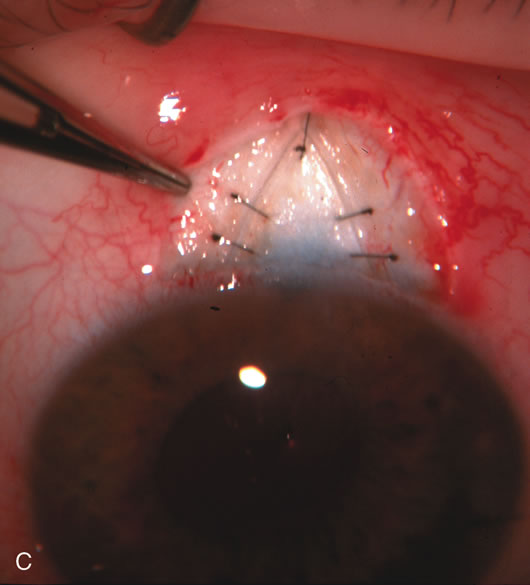

Fig. 8. Bleb appearance after limbus-based versus fornix-based conjunctival flaps. Even though the IOP is thought to be equivalent between limbus and fornix-based conjunctival flaps, the final bleb appearance varies considerably. A. During a limbus-based approach, an incision through conjunctiva 10 mm posterior to limbus will sever through multiple arterial vessels, increasing the likelihood of an avascular bleb. B. The tissues are dissected down to the sclera further cutting feeder vessels from Tenon's capsule. C. The wound is closed inciting a cascade of wound healing events that may ultimately lead to scarring producing a barrier to aqueous flow. D. This leads to walling off of a bleb that has lost some of its overlying vascularity (pale cystic avascular bleb). E. During a fornix-based conjunctival approach, the incision is made at the limbus and tissues undermined. F. The incision is closed at the limbus; no conjunctival vessels are severed over the bleb area. G. This fosters the formation of a shallow diffuse pale bleb with a normal vessel pattern.